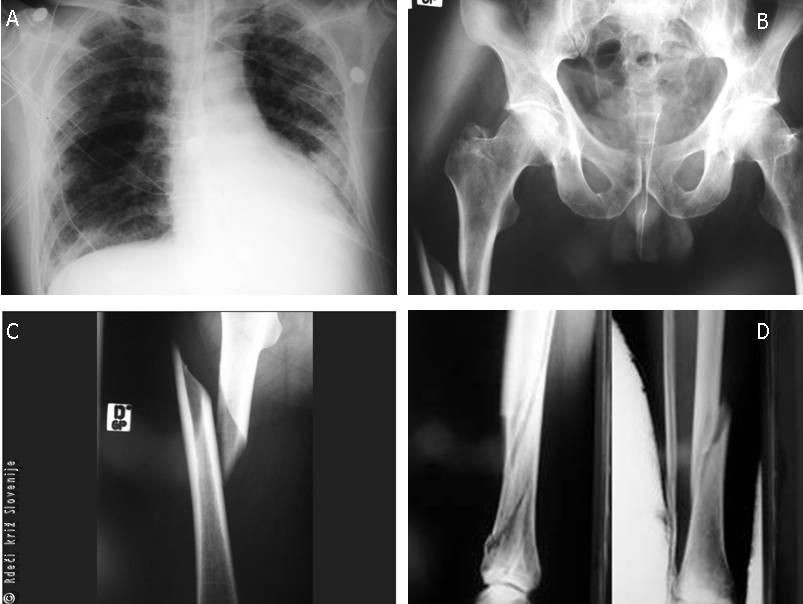

Slika 7

A – RTG pljuč po vstavitvi torakalnih drenaž (obojestransko je videti zasenčenje pljuč, kar je posledica udarnin pljuč obojestransko, vidne so tudi cevi torakalnih drenaž);

B – RTG medenice (zlom vej sramnice brez dislokacije obojestransko);

C – RTG desne stegnenice(spiralni zlom na meji med zgornjo in srednjo tretjino);

D – RTG desne goleni (večfragmentni zlom spodnje tretjine goleni).